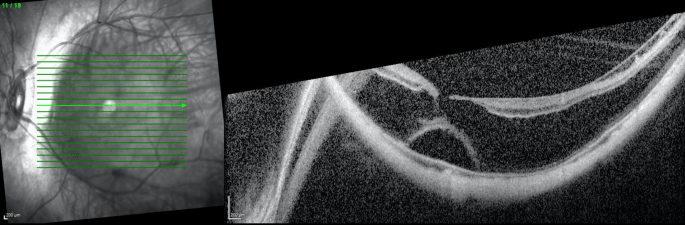

Severe myopic macular schisis with shallow macular RD and macular hole.

54 YO BM w -20d myope, lost central vision OD years ago from atrophic macular atrophy due to severe macular staphiloma, now the OS is starting to do the same. What are the options? Macular buckling? Vitrectomy with gas or oil? What does chronic eye rubbing have to do with it?